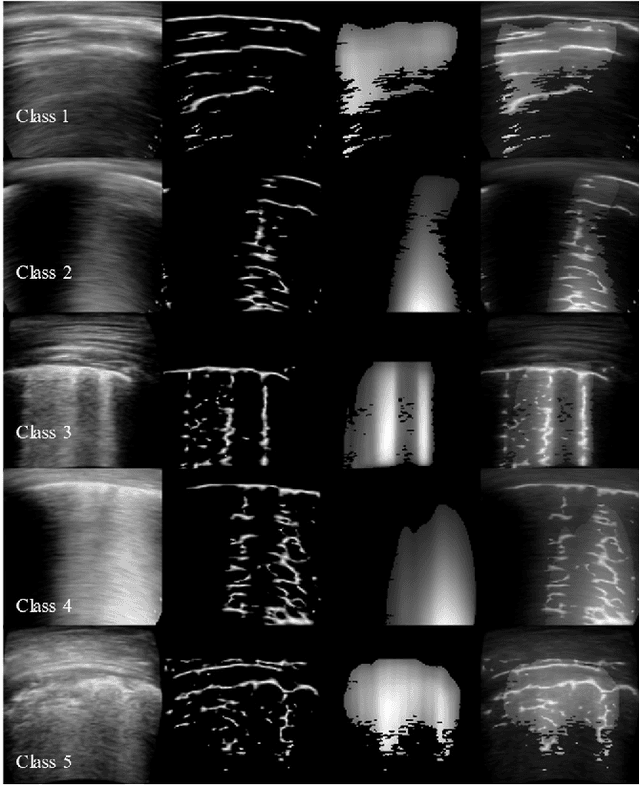

Abstract:Ultrasound is fast becoming an inevitable diagnostic tool for regular and continuous monitoring of the lung with the recent outbreak of COVID-19. In this work, a novel approach is presented to extract acoustic propagation-based features to automatically highlight the region below pleura, which is an important landmark in lung ultrasound (LUS). Subsequently, a multichannel input formed by using the acoustic physics-based feature maps is fused to train a neural network, referred to as LUSNet, to classify the LUS images into five classes of varying severity of lung infection to track the progression of COVID-19. In order to ensure that the proposed approach is agnostic to the type of acquisition, the LUSNet, which consists of a U-net architecture is trained in an unsupervised manner with the acoustic feature maps to ensure that the encoder-decoder architecture is learning features in the pleural region of interest. A novel combination of the U-net output and the U-net encoder output is employed for the classification of severity of infection in the lung. A detailed analysis of the proposed approach on LUS images over the infection to full recovery period of ten confirmed COVID-19 subjects shows an average five-fold cross-validation accuracy, sensitivity, and specificity of 97%, 93%, and 98% respectively over 5000 frames of COVID-19 videos. The analysis also shows that, when the input dataset is limited and diverse as in the case of COVID-19 pandemic, an aided effort of combining acoustic propagation-based features along with the gray scale images, as proposed in this work, improves the performance of the neural network significantly and also aids the labelling and triaging process.